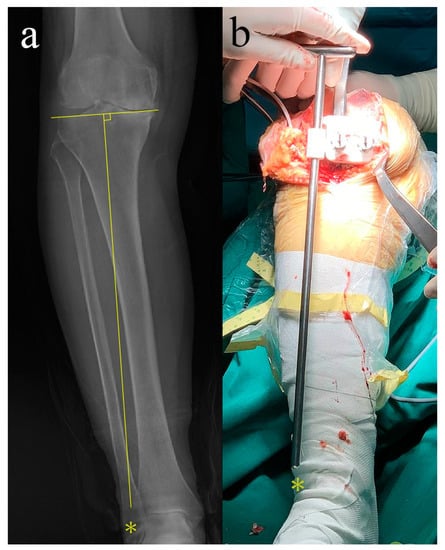

2.2. Design and Manufacturing of PSI

2.4. Intraoperative Positioning of PSI